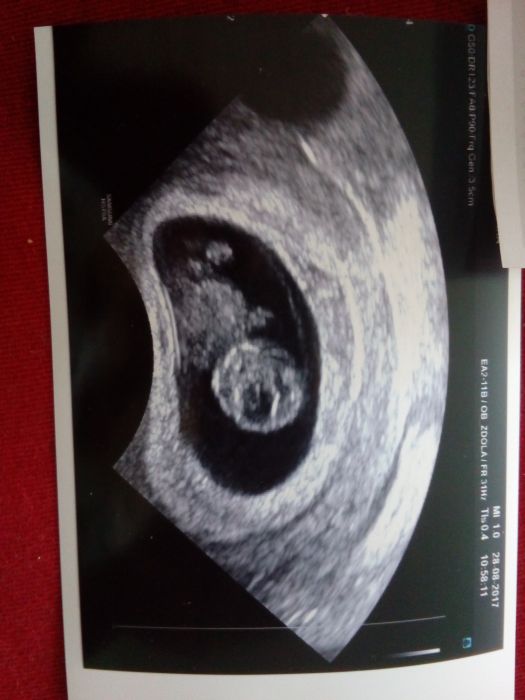

nicméně dovca byla úžasná!!!. První kontrola v 7+1 dopadla dobře, srdíčko už bouchalo. V práci jsem za týden začla trochu krvácet a našli mi hematom 2x2cm, ale mimco ok

. Dostala jsem neschopenku, utrogestan a Ascorutin, klidový režim a dnes po týdnu kontrola, která dopadla na výbornou, hematom se vstrebal a doktor i já nevericne zíral

Dnes jsem tedy 9+1, medvídek má 2,47cm, a krásně se už kroutil

nádhera!!! Další kontrola v první poradne 13.9. už teď se moc těším az ten zázrak zase uvidím